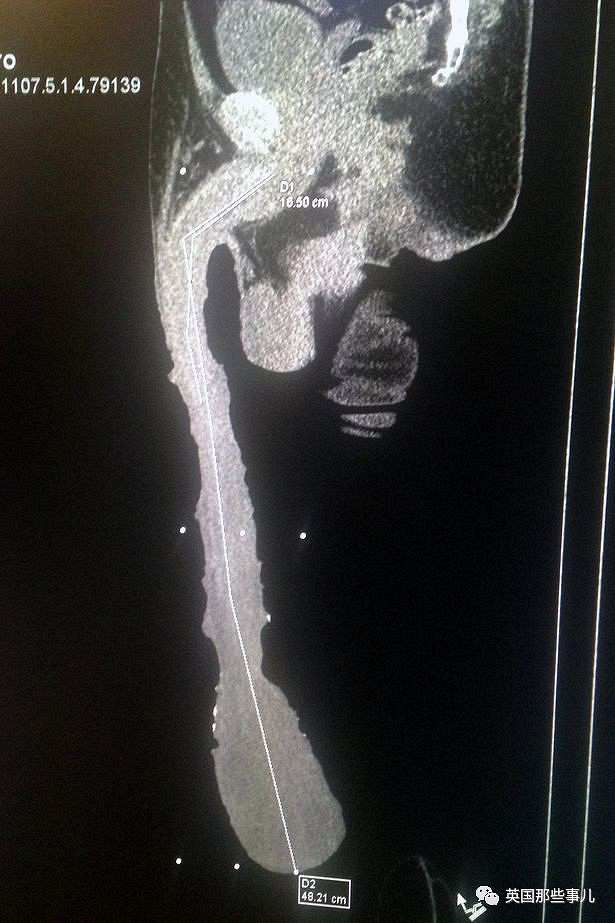

男孩左侧股骨骨折x光片请大家积极转发,"小飞侠"想妈妈了!